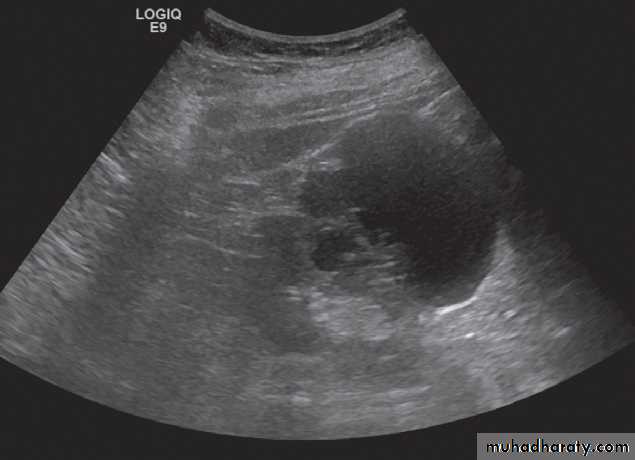

Ultrasound Dilatation of the pelvicaliceal system ( hydronephrosis ) is demonstrated sonographically as a multiloculate fluid collection in the central echo complex, caused by pooling of urine within the distended pelvis and calices .

Major DDX are multiple renal cysts. With prolonged obstruction, thinning of the cortex due to atrophy will be seen.

Some causes of obstruction are identifiable (e.g. carcinoma of the bladder or a stone at the vesicoureteric junction), it is often not possible to determine the cause of urinary tract obstruction at ultrasound examination.